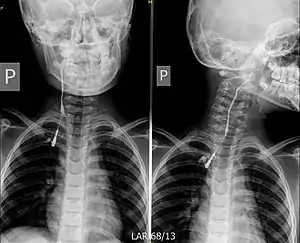

| Fistulogram (sinogram) of a right branchial cleft sinus. | |